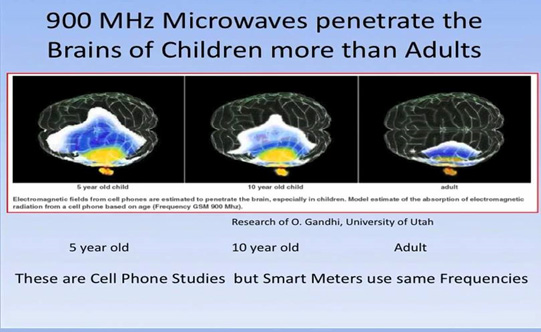

Below is a picture from the University of Utah researcher Om Ghandi showing how far cell phone radiation penetrates into the brain. Studies by University of California at Santa Cruz Professor of Nuclear Policy Daniel Hirsch show that the whole-body cumulative radiation exposure from wireless meters is 100â160 times more than cell phone exposure.

The latest cell phone research shows that people who used wireless phonesâcell or cordlessâfor more than a year were at 70% greater risk of brain cancer as compared to those who used wireless phones for a year or less. Those who used wireless phones for more than 25 years were at a 300% greater risk of brain cancer. As we have seen above, smart meters emit far more radiation than al other sources combined. The son of one of our members has just been diagnosed with a glioblastoma. This kind of cancer, once rare, is increasing dramatically in the population. His cancer is in his left temporal lobe, right where most people hold their cell phone.